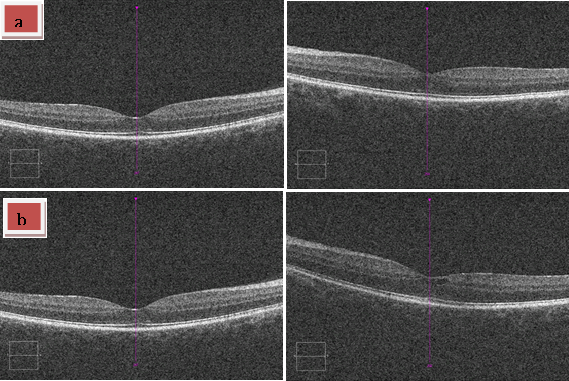

| Figure 4: Macular OCT was normal after treatment in case 1. Patient reported in case 2 condition improved regarding the presence of serous detachments/subretinal fluid although a few intraretinal peri-foveal cysts still remained. a) Patient 1. b) Patient 2. |